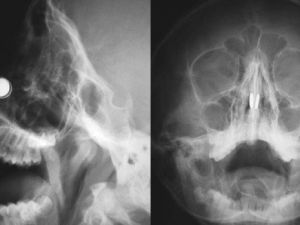

Kronik burun tıkanıklığı yaşam kalitesini düşürüyor